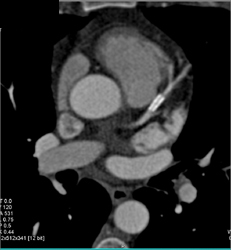

Patent LAD Stent